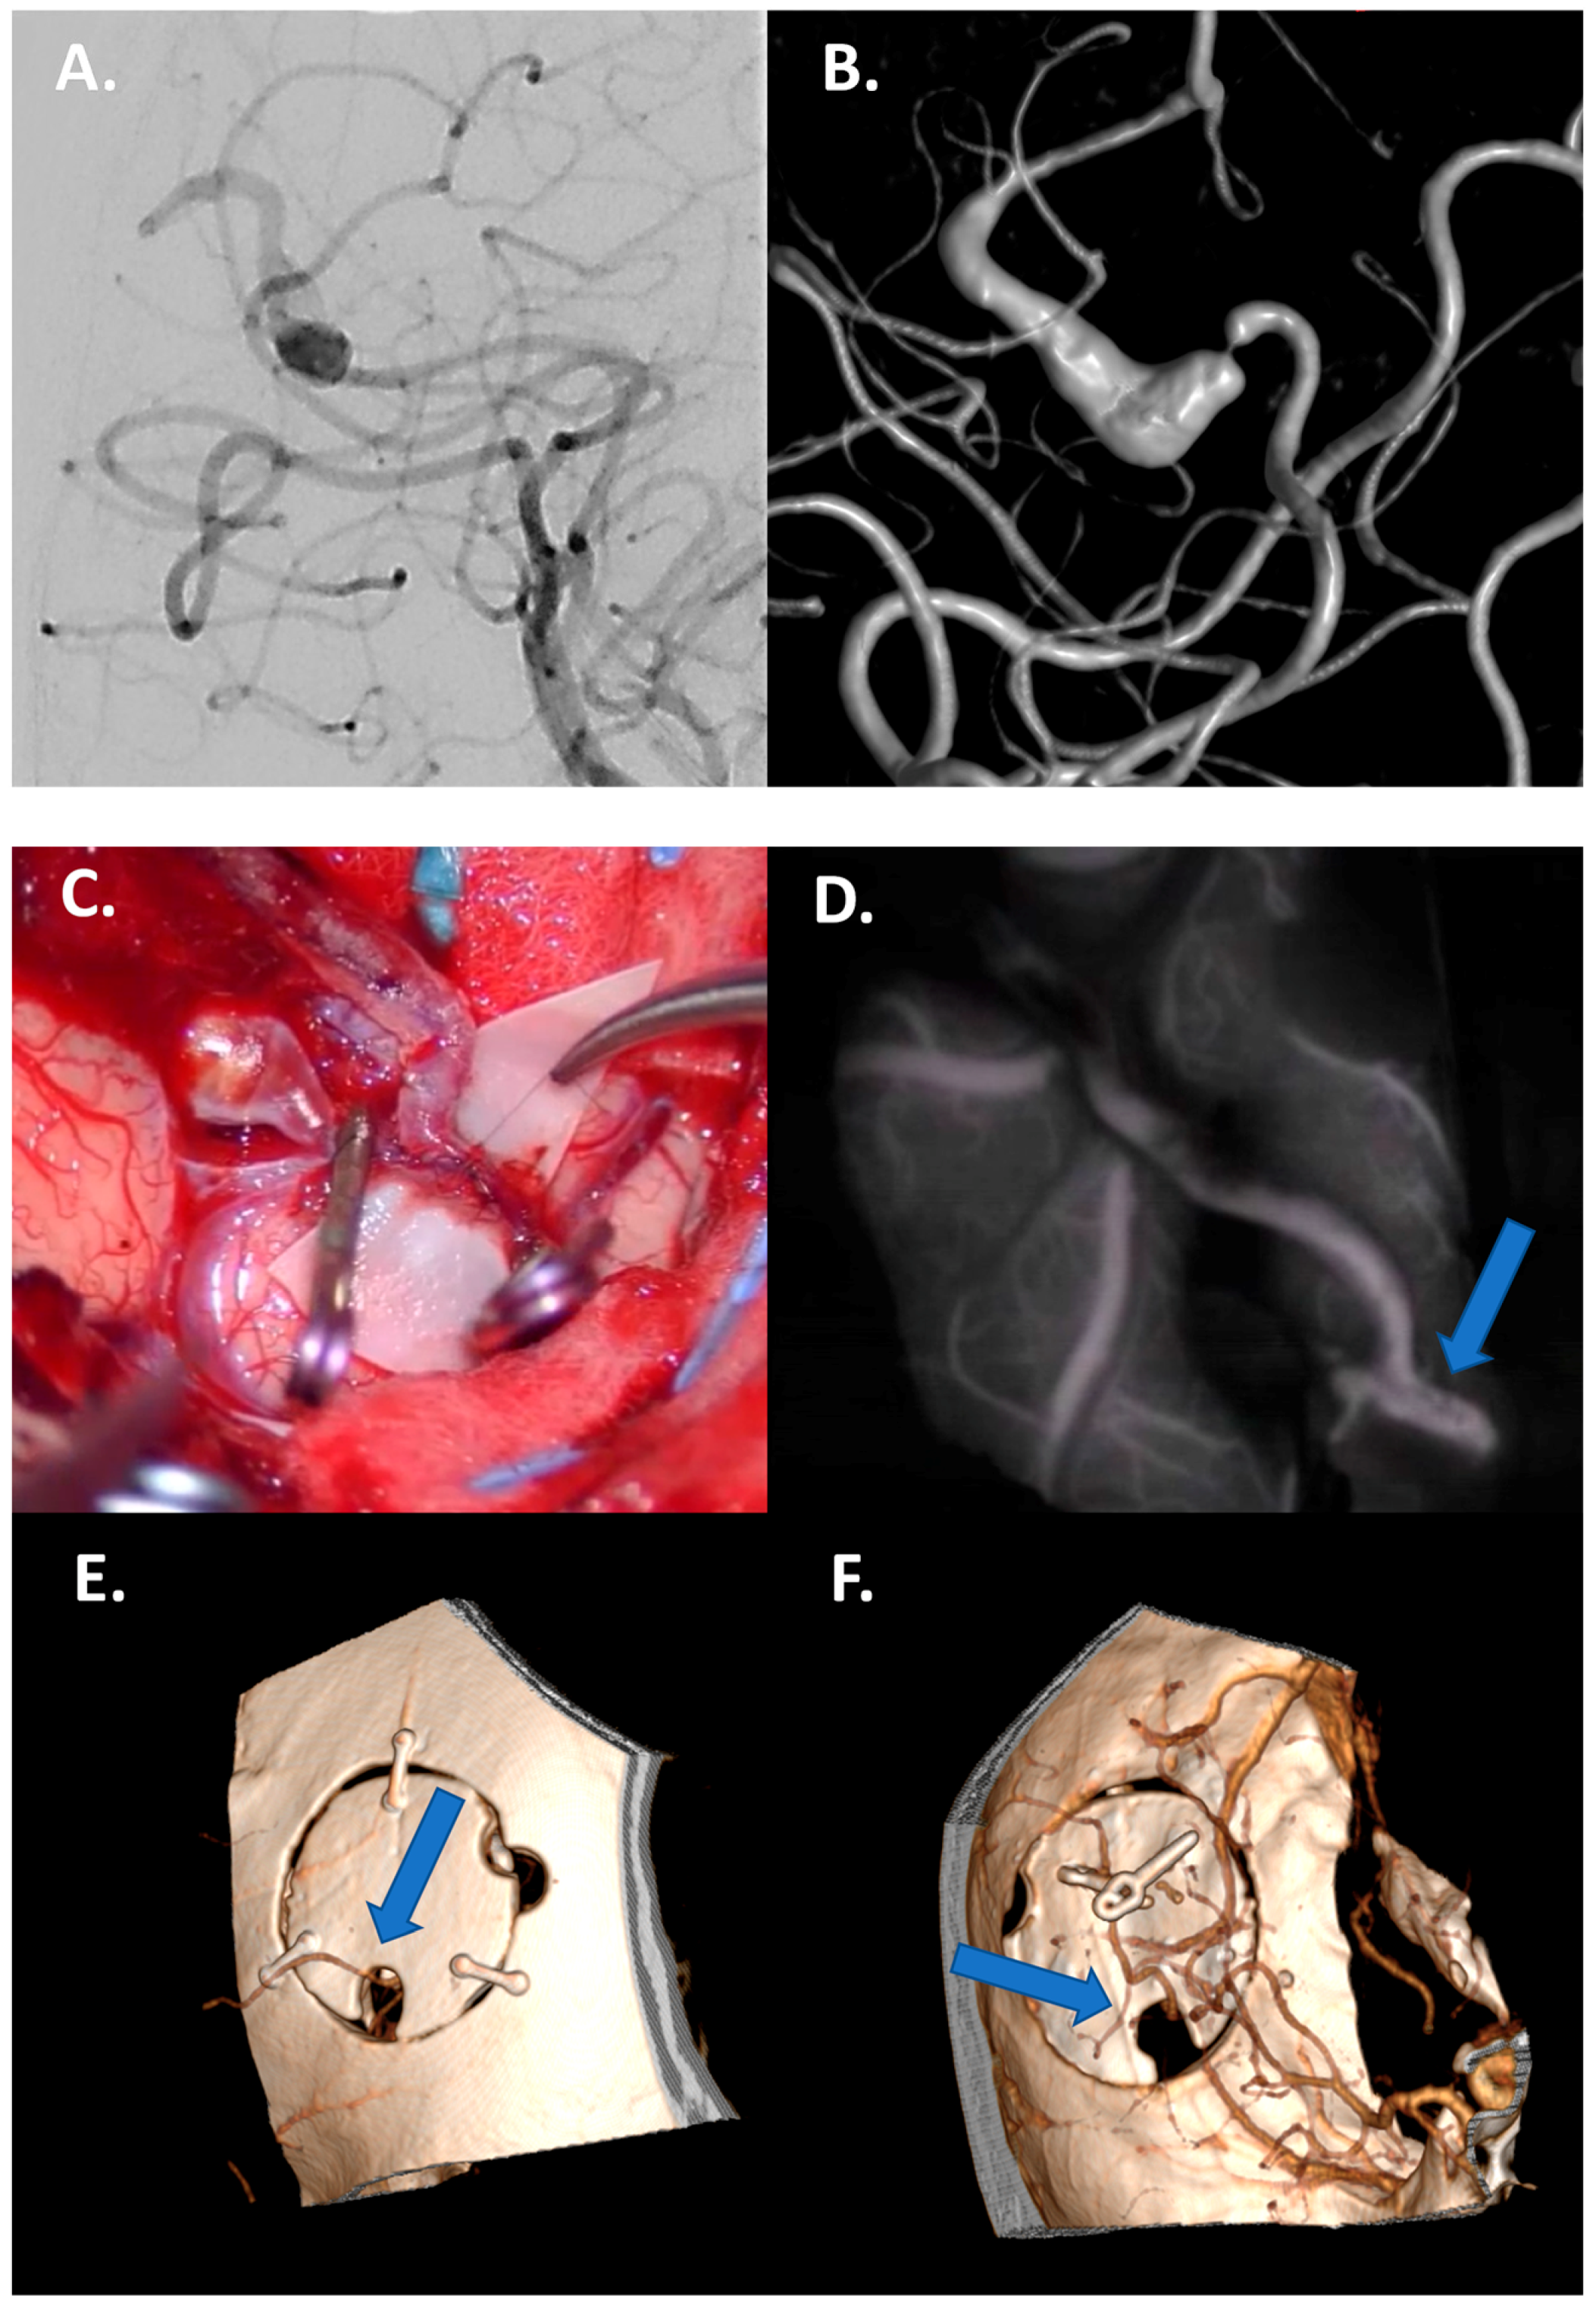

4.3.1. Large/Giant Aneurysm Size and Fusiform Shape

4.3.2. Vessels Branching from the Dome

4.3.3. Thrombosed Aneurysm and/or Previously Treated Aneurysms